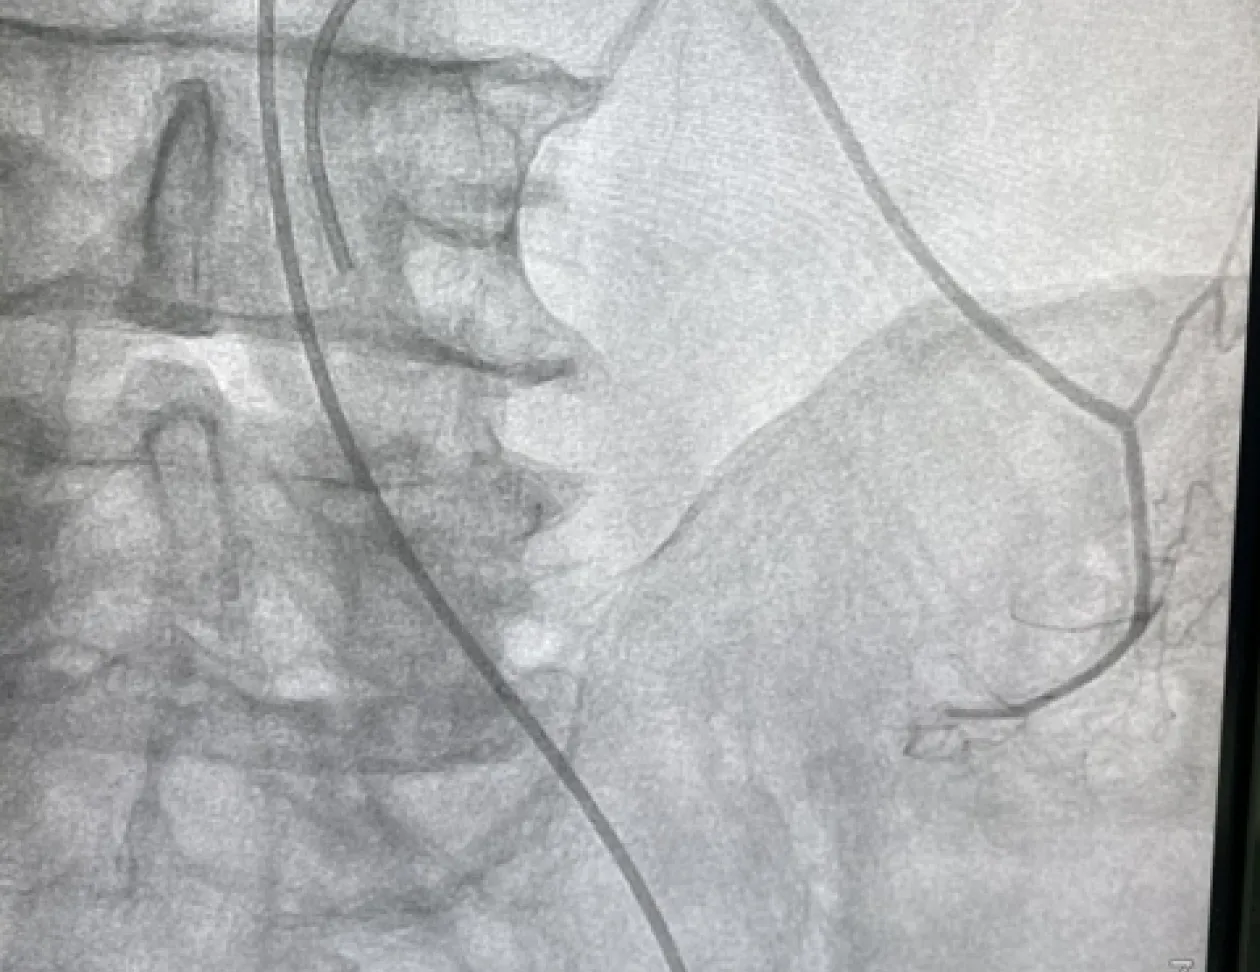

— Сам метод емболізації застосовується не лише в онкології, а й в інших галузях медицини. Наприклад, за кровотеч, хронічних гнійних захворювань, доброякісних новоутворень на жіночих статевих органах, — розповідає завідувач відділення торакальної хірургії Чернігівської обласної лікарні Олег Лузан. — Якщо говорити про хіміоемболізацію, то це певне відгалуження ендоваскулярної хірургії (напрямок сучасної медицини, що спеціалізується на проведенні малотравматичних оперативних втручань. — Авт.). Хіміоемболізація проводиться на ангіографі – апараті для дослідження та оперування судин.

– Хіміомемболізація полягає в тому, що в пухлину через судини вводиться хіміопрепарат. Якщо взяти для прикладу патології легень, то робиться прокол у паху і через стегнову артерію вводиться катетер, який потім заводиться в аорту, аж у грудну частину. І вже там знаходиться судина, яка живить пухлину. Прямо в цю пухлину вводиться хіміопрепарат, минаючи печінку та інші органи. Після цього посудина емболізується, інакше кажучи, закупорюється спеціальними мікрочастинками-емболами. Таким чином досягається подвійний ефект: збільшується концентрація хіміопрепарату в пухлини і водночас припиняється кровообіг у цій пухлині. В результаті вона зменшується, і трапляються випадки, коли за кілька сеансів хіміоемболізації вдається навіть перевести пацієнтів з неоперабельного стану в операбельний.

В Україні, окрім Чернігова, на регулярній основі такі операції проводяться лише у Харкові, Кропивницькому та Вінниці. Складність операції полягає в тому, що важко знайти необхідну посудину, адже вони бувають діаметром до 1 мм. Тому від лікаря потрібна філігранна точність та колосальний досвід. Спеціалістів, які можуть виконувати емболізацію, в Україні є одиниці. Один із них – доктор медичних наук, завідувач відділення інтервенційної рентгенології Інституту невідкладної хірургії ім. Зайцева Юрій Володимирович Авдосьєв. Він спеціально приїжджає з Харкова до нас проводити операції з емболізації. Я чи хтось із моїх колег-хірургів виступаємо в ролі асистента.